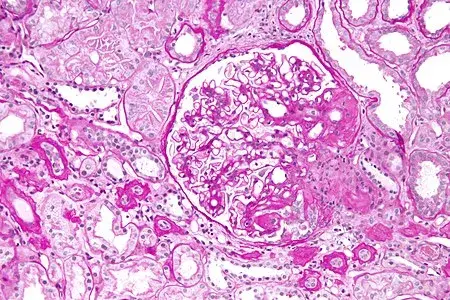

A hemodiafiltração pode aumentar significativamente a depuração de diversos medicamentos, levando a subdosagem quando usamos protocolos baseados em hemodiálise convencional. Entender a farmacocinética da droga e a prescrição da HDF é essencial para evitar falha terapêutica e ajustar corretamente as doses.